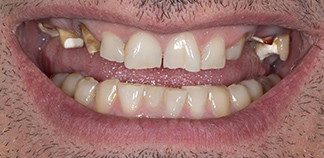

Результаты лечения пациентов

До лечения

Жалоба на отсутствие нормальных жевательных зубов.

Как лечили

Удалены корни разрушенных зубов. Установлены импланты, проведена художественная реставрация зубов.

Лечащий врач

БОЙКО Артемий Петрович